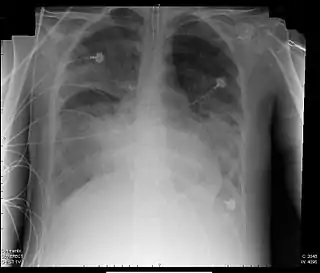

![]() Radiografía de tórax de paciente con SDRA | ||

SDRA fue definido en términos del ratio o cociente entre la presión parcial de oxígeno arterial (PaO2) y la fracción de oxígeno inspirada (FiO2) por debajo de 200 mmHg, y la presencia de infiltrados alveolares en la ex de tórax. Estos infiltrados pueden parecer semejantes a los vistos en la insuficiencia cardíaca con edema pulmonar, pero la silueta cardíaca (tamaño) es normal en el SDRA. También la presión de enclavamiento pulmonar es normal (por debajo de 18 mmHg) en el SDRA, estando aumentada en caso de edema pulmonar cardiotónico.[6]

| Opacidades bilaterales que son "consistentes con edema pulmonar" en radiografía de tórax o TC de tórax. | Existe poca fiabilidad interobservador en interpretar la Rx de tórax por la presencia de edema. Para dirigir este asunto, la definición de Berlin ofrece criterios más explícitos (ejemplo; opacidades no deben ser completamente explicadas por derrame, atelectasia lobar o pulmonar, o nódulos o masas), con radiografía ilustrativa proporcionada. |